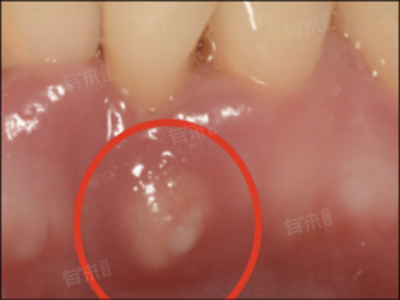

牙槽骨突出怎么办

1、正畸治疗:正畸治疗是矫正牙槽骨突出的有效方法之一,通过佩戴矫治器,可以逐渐调整牙齿和牙槽骨的位置,达到正常的咬合关系和面部形态。正畸治疗需要根据患者的具体情况制定个性化的治疗方案,并遵循医嘱按时佩戴矫治器和进行复诊。

2、手术治疗:对于重度突出或伴有骨性问题的患者,正畸治疗可能无法达到理想的矫正效果。可以考虑采用手术治疗的方法,如正颌手术等,通过调整颌骨的位置和形态来改善牙槽骨突出的问题。